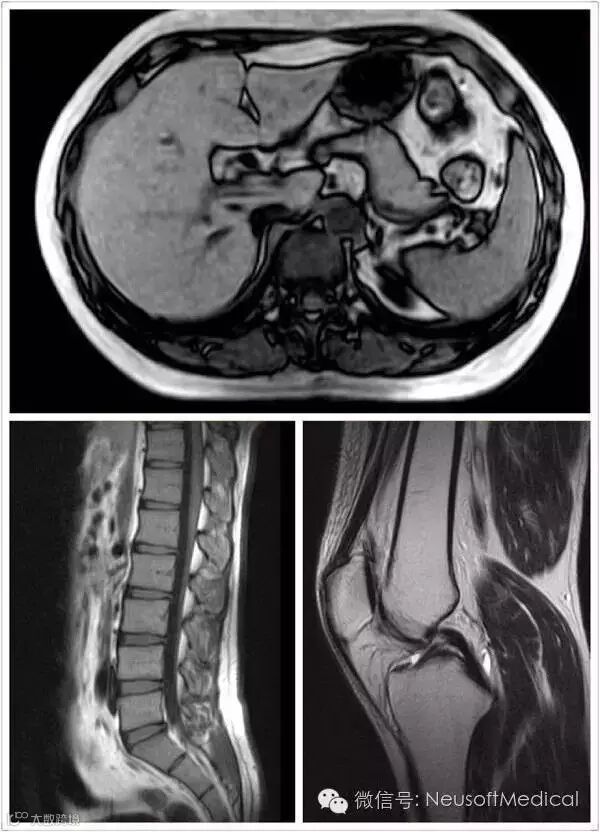

Superstar 0.35T磁共振图像质量优异,永磁之王当之无愧!

所以虽然是低场磁共振,但是Superstar成为国际顶尖学术会议的座上客。东软医疗在沙特的一名Superstar用户,不仅在该设备上写出了学术论文《水脂分离技术(Dixon)在低场磁共振膝关节软骨缺损检查中的应用》,还向国际顶级学术会议欧洲放射学年会(ECR)和国际医学磁共振学会(ISMRM)投稿。令人兴奋的是,两个学术会议都选中了这篇文章,并邀请作者参会做学术讲座。